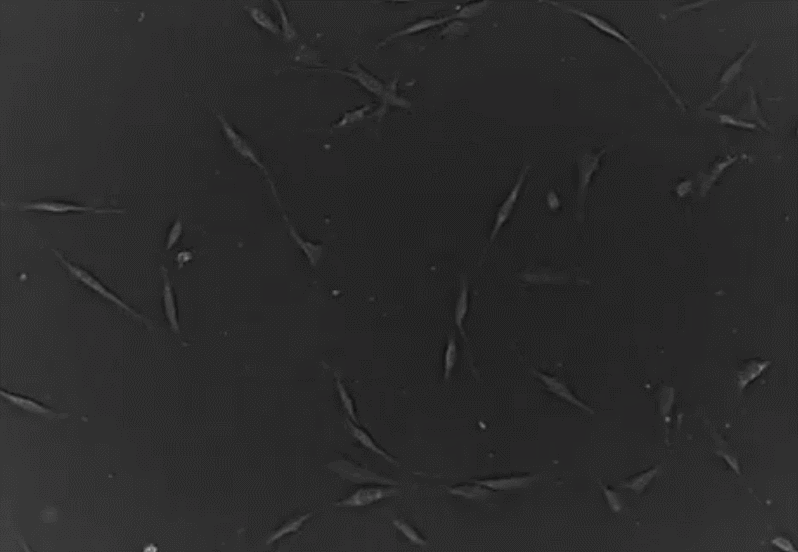

干細胞是一類具有多向分化潛能和自我復制功能的原始的未分化的細胞,在一定的條件下,干細胞可以分化成為人體不同組織的細胞,因此科學家稱之為“萬能細胞”。

圖片